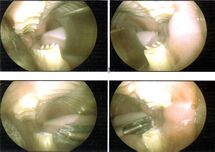

Molar spurs

- Pete the Vet. (2017). 3-year-old lop Button had a single sharp spur

- Bird and Exotic Animal Clinic. (2018). Facebook video of a mouth exam of a sedated rabbit with molar spurs.